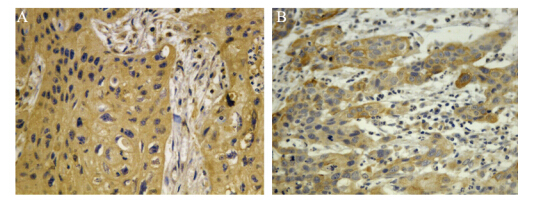

免疫组织化学检测结果显示,hTERT蛋白阳性产物主要定位于细胞质,见图 1A。食管癌组织中hTERT蛋白阳性表达率显著高于不典型增生及正常组织(P=0.00),见表 1。食管癌组织中hTERT蛋白表达与不同临床参数之间的关系,见表 2,其中有纤维膜浸润者显著高于无纤维膜浸润者(P=0.00)。

| A: hTERT protein(IHC×400); B: NF-κB protein(IHC×400) 图 1 食管癌组织中hTERT与NF-κB蛋白的表达 Figure 1 hTERT and NF-κB protein expression levels in esophageal cancer tissues detected |

NF-кB蛋白阳性产物主要定位于细胞质和细胞核,高表达主要见于癌组织呈棕黄色颗粒散在分布,见图 1B。不典型增生和切缘正常组织低表达。食管癌组织中NF-κB蛋白阳性表达率显著高于不典型增生及正常组织(P=0.00),见表 1。食管癌组织中NF-κB蛋白表达与不同临床参数之间的关系见表 2,其中有纤维膜浸润者显著高于无纤维膜浸润者(P=0.01)。